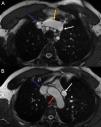

CMRI revealed biventricular dilatation and paradoxical septal motion compatible with volume overload. Balanced steady-state free precession sequences in axial planes showed an anomalous vein oriented vertically and lateral to the aortic arch, communicating with the innominate vein (Figure 1), and a normal-sized coronary sinus.

(A) Axial view, balanced steady-state free precession. Blue arrow – superior vena cava; yellow arrow – innominate vein; white arrow – anomalous vertical pulmonary vein. (B) Axial view, balanced steady-state free precession. Blue arrow – superior vena cava; red arrow – aortic arch; white arrow – anomalous vertical pulmonary vein.